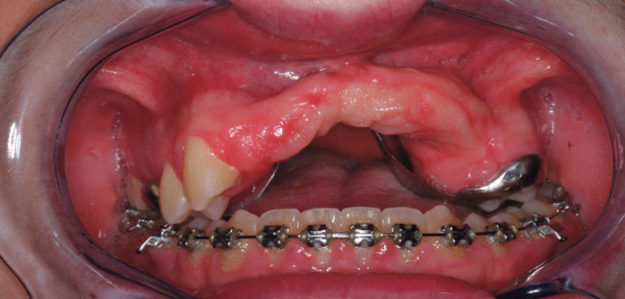

Dimension verticale de la face et prise en charge du sourire gingival

Non classéPar domguillemet14 mai 2018Laisser un commentaire